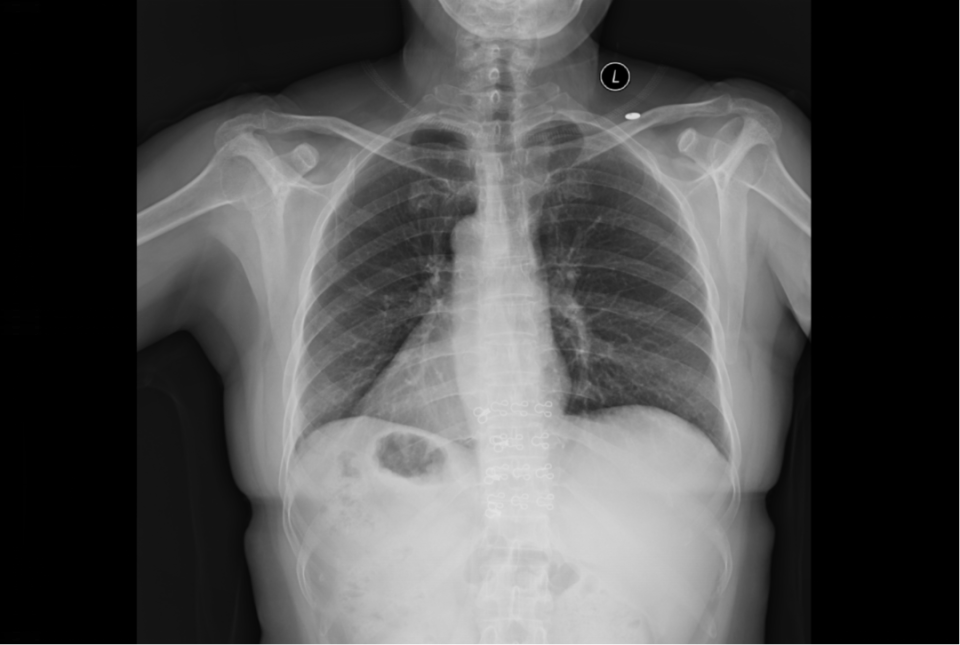

全内脏反位

什么是“全内脏反位”?简单来说,张女士的心脏、肝脏、胆囊、脾胃等所有胸腹腔器官,位置都与正常人完全左右对调。就像照镜子时看到的自己,医学上形象地称之为“镜面人”。

图片

这种先天变异的发生率极低,大约每万人中仅有1例。对于普通人来说,这只是一个有趣的医学名词;但对于即将接受手术的张女士和她的主刀医生来说,这意味着巨大的挑战。